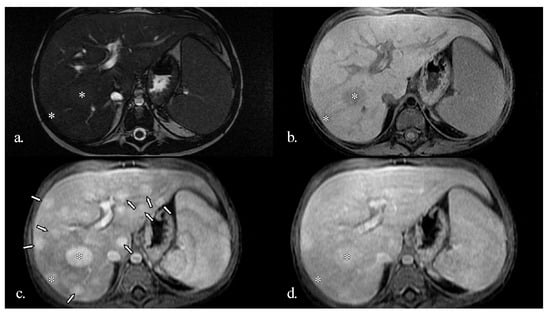

In addition to standardized lateral cephalometric radiographs, comprehensive assessment using dental cone-beam computed tomography (CBCT) and CT has become commonplace in the diagnosis and treatment of jaw deformities. Simulation based on cephalometr...